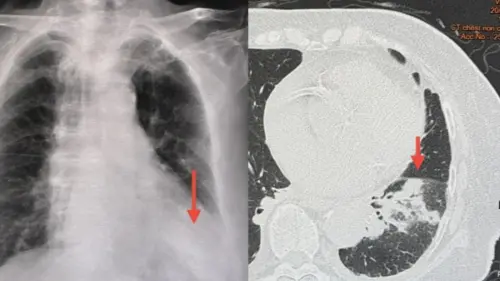

婦女到醫院接受檢查,胸部X光顯示她的左下肺部異常,但痰液與血液培養未檢測到結核菌或細菌感染。儘管接受抗生素治療,但病情未見好轉,因此在1月19日轉院。

但轉院後婦女的狀況更糟,醫師發現婦女的血氧濃度已降至87%,需要接受氧氣治療,並進一步接受電腦斷層掃描(CT scan),發現她的左下肺部有白色陰影,同時胸膜腔內有少量積液,最終推斷是退伍軍人病(Legionnaires' disease)。

▲醫生斷定此名女子染上「退伍軍人病」併發肺炎。(圖/翻攝自臉書) 瑪努醫師指出,由於該婦女入住的房間長時間無人居住,因此退伍軍人菌可能已在冷氣系統或儲水設備中滋生。當患者開啟冷氣,或使用淋浴設備時,細菌可能隨水霧或氣溶膠散播,導致吸入性感染。